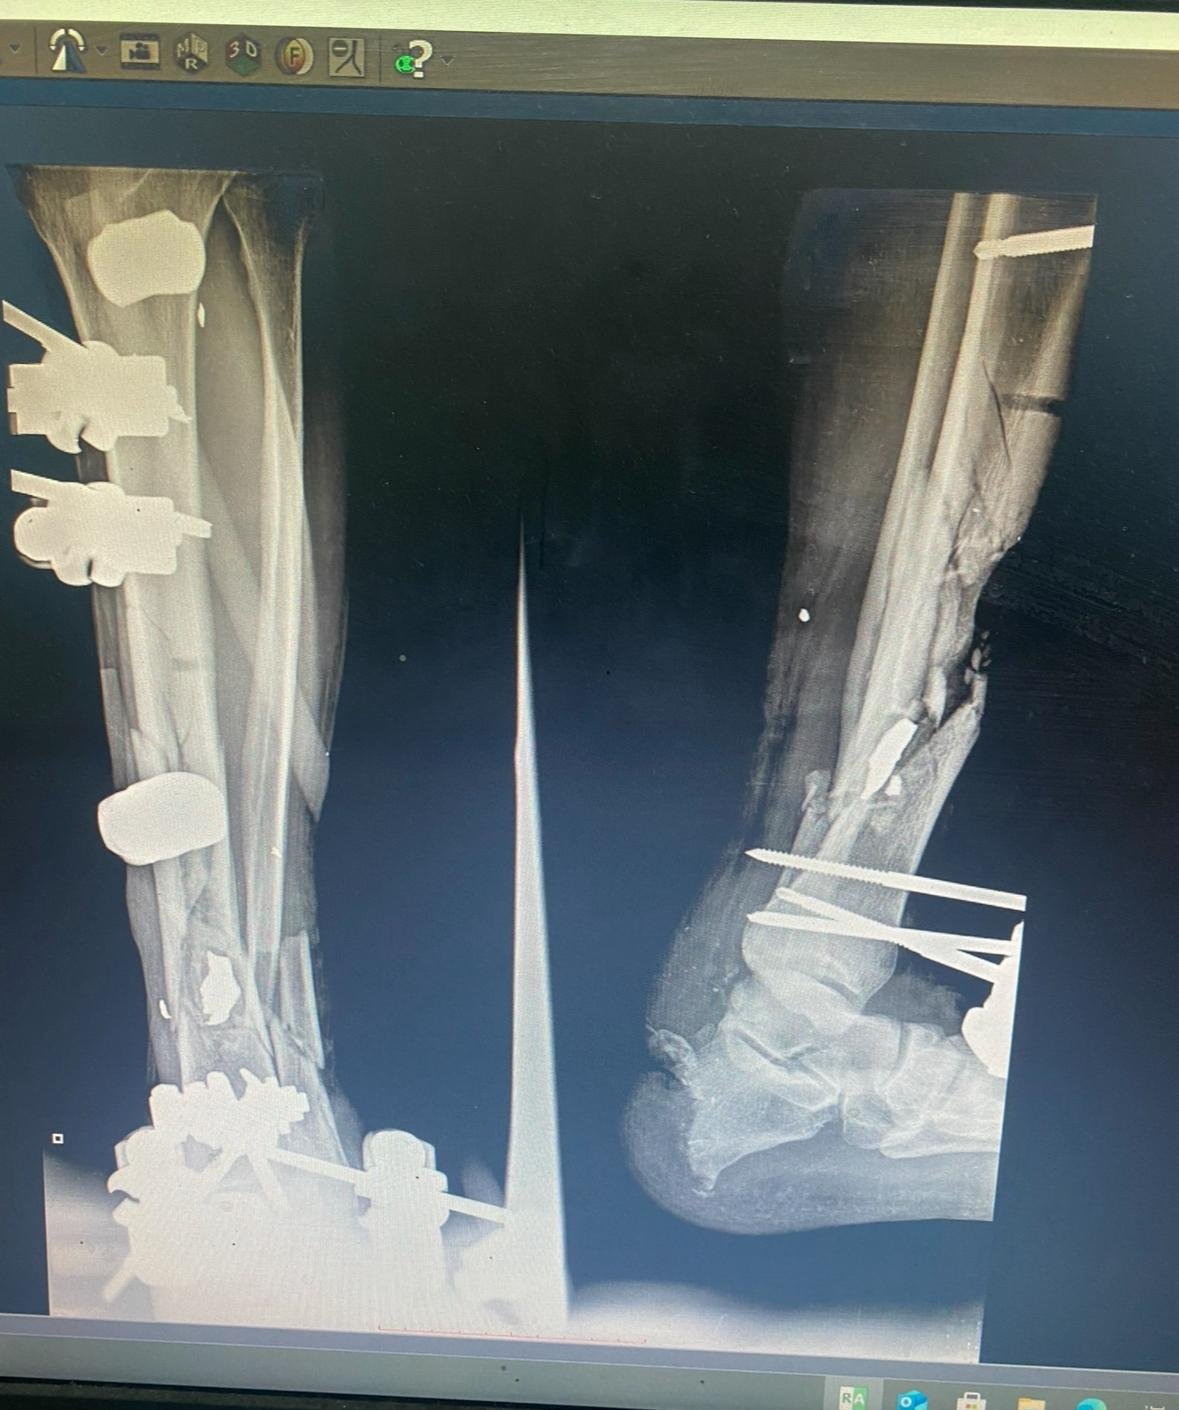

Every one of the patients stated they were waiting in line in the sun (100+ degree F weather) until quadcopters came flying overhead and then they lowered and began firing at all their legs. Many ran, some were trampled, and some were hit by quadcopter fire. The injured that survived ended up on the floor of the ER writhing in pain in an environment with no morphine, limited blood products and no sterility. Tibias and femurs shatter by gunfire and a few vascular injuries putting limbs at risk for amputation.

On top of it, the kids were gaunt… no muscle mass… cachectic. A good portion of them will be maimed forever. Their households will lose the young boys who they depend on to help carry things and future heads of households will now require assistance themselves to survive their injuries and likely a lifelong disability. The injuries were all similarly aimed… everyone in the room recognized the strategy.